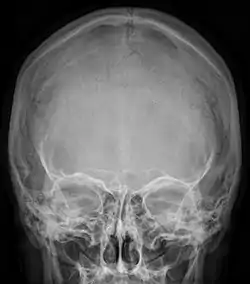

![]() Radiograph of the skull showing an interparietal bone between the occiput and parietal bones | |

In humans, it corresponds to the upper portion of the squama of the occipital bone that lies superior to the highest nuchal line and is completely fused to the supraoccipital. However, in some individuals this portion remains separate from the rest of the occipital bone throughout life. In such cases, this separate bone is particularly referred as Inca bone. Inca bones in humans were first found in the skulls of contemporary indigenous peoples of the southern Andes as well as in those of mummies of the Inca civilization. Although the Inca bone was originally encountered as a variation in South American and Latin American cranial remains, the variation occurs in people from all geographic regions of the world and is by no means indicative of South/Latin American origin.